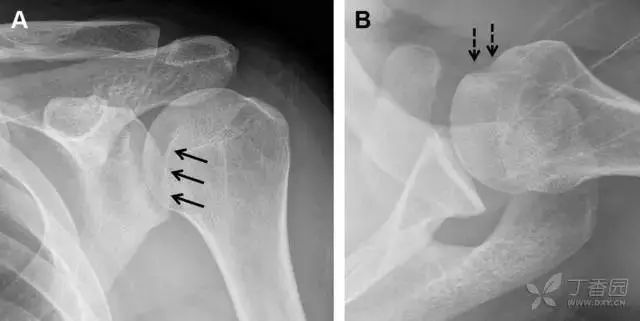

单纯肱骨大结节骨折

与其它肱骨近端骨折不同,单纯肱骨大结节骨折常发生于年轻人。肱骨大结节骨折常由撞击或剪切/撕脱损伤所致:

在常规前后位片上,大结节与肱骨头重叠,骨折不易发现,外旋位前后位片有助于诊断。

图 1 大结节骨折。(A)脂肪抑制序列斜冠状位 MRI,显示肱骨大结节线性骨折无移位(箭头)与周围骨水肿;(B)外旋位前后位(AP)片,证实大结节骨折(箭头),典型的骨折愈合过程中的骨吸收表现;(C、D)初诊时内旋位、外旋位前后位片,初诊时漏诊,仔细回顾影像,内旋伞下可见双密度影(椭圆),骨皮质中断(箭头)